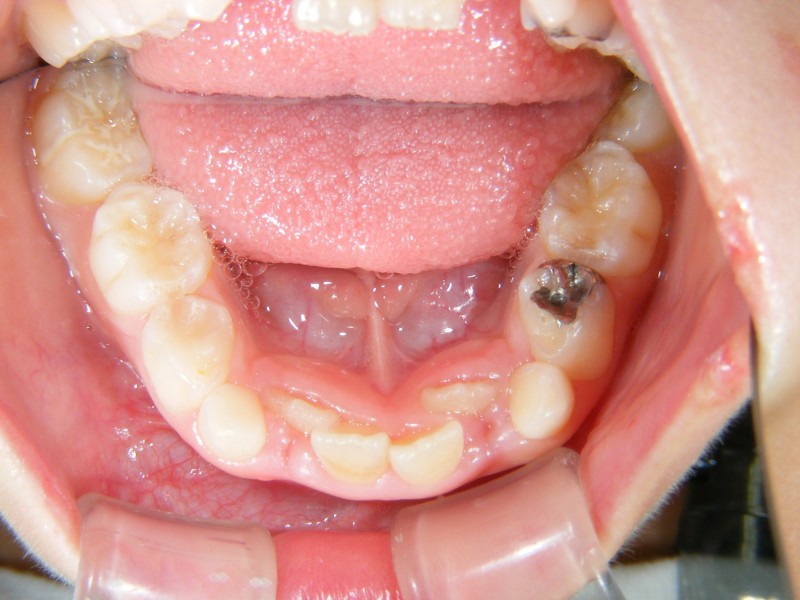

↑こちらは、小学校1年生の患者さんです。

主訴は、前歯の凸凹です。

あごの大きさと、歯の大きさのアンバランスにより起こります。

↑こちらが初診時。小学1年生。